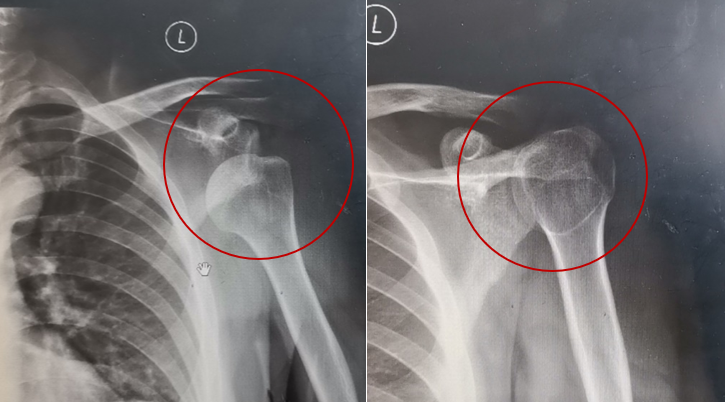

此前,27岁的小蔡在一个“高档”泰式SPA会馆按摩,当按摩师按到肩关节时,先做了一些旋转、撑起的动作,然后一提拉,“咯噔”一声,悲剧发生了。小蔡的左肩当时就不能动了。X线片显示,小蔡的左肩关节脱位,经复位治疗后,小蔡还要经历6周的肩关节固定、制动休息,也就是“打石膏”。